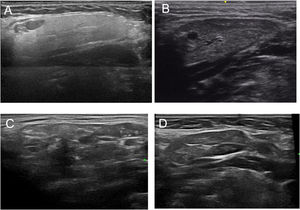

Based on all of the possible glandular aspects assessed with US (hyperechoic lines, number and size of hypoechoic images, etc.), we evaluated only parenchymal homogeneity for diagnostic purposes in accordance with the available literature.10 These findings were graded based in the experience of the authors with a 4 grades semiquantitative score, quite similar to the proposed by OMERACT group in 20192 that considers parenchymal homogeneity ranging from 0 to 3 and can be assessed in both parotid (Fig. 1) and submandibular (Fig. 2) glands. The definition of each grade is specified below: Grade 0: homogeneous normal glandular parenchyma; grade I: minimal glandular heterogeneity without hypoechoic images; grade II: moderate parenchymal heterogeneity with hypoechoic images; grade III: severe heterogeneity with hypoechoic lesions in the entire glandular parenchyma.